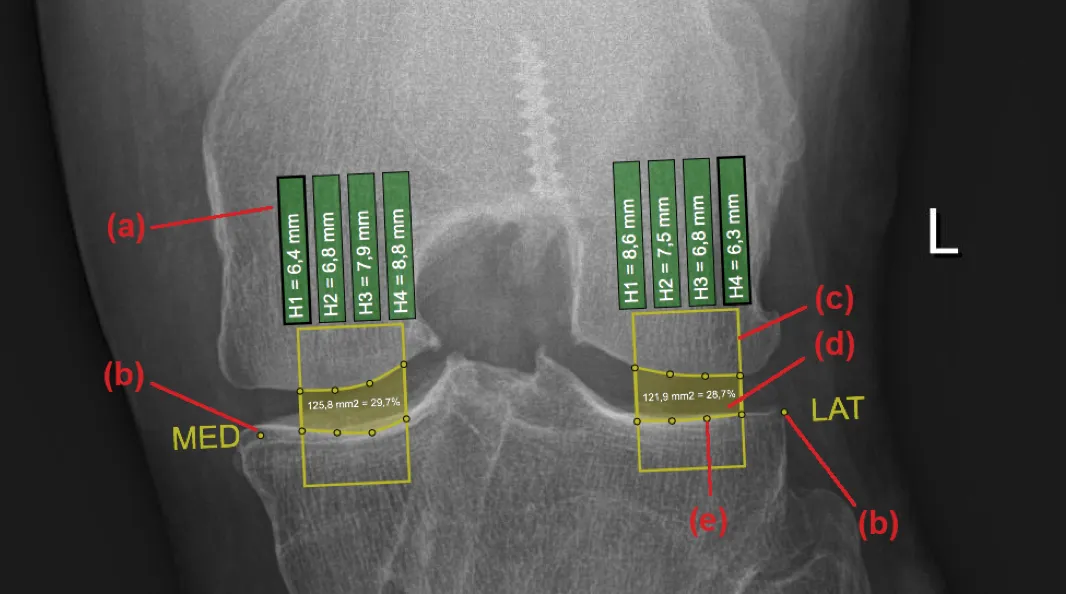

Developed an interactive clinical visualization system at ImageBiopsy Lab for analyzing osteoarthritis progression in knee joints. The platform integrated machine-learning models for automated landmark detection and quantitative measurement extraction from radiographic images, enabling structured visualization of joint-space narrowing and anatomical changes over time. The system translated computational imaging models into an accessible web-based analytical interface for research and clinical evaluation. The project formed the basis of my Bachelor’s thesis under the supervision of Prof. Eduard Gröller.